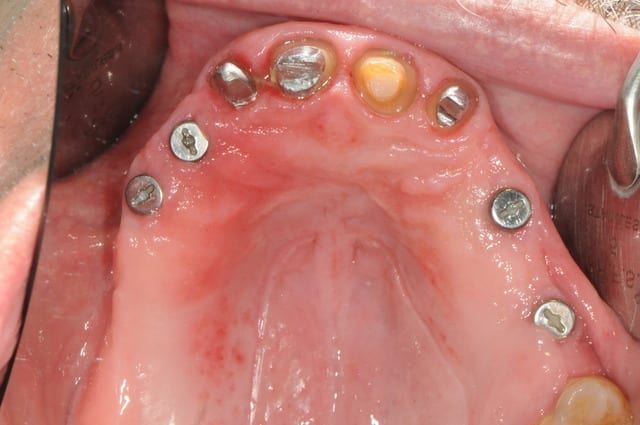

si ça peux alimenter ta réflexion...

manque d'intelligence de ma part j'ai pas fait de photo du cas au tout départ. mais la première photo devrait vous donner une idée du reste...

la suite c'est pose 4 implants, ceramique, stellite sur locators (beaucoup moins couteux qu'une barre et plus facile à nettoyer)